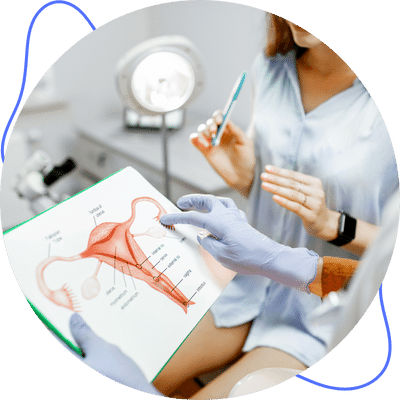

Especialista en:

Obstetricia

Cirugía Ginecológica

Interrupción del embarazo

Climaterio y Menopausia